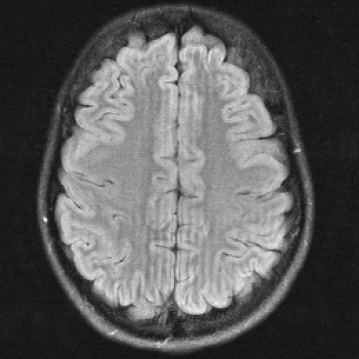

2.1 Illustration of the failure of common FR-IQA measures on synthetic image degradations

In Figure 1 we show a toy example of misjudgments that occur when evaluating the quality of a 2D MRI scan compared to degraded versions of the same image with standard measures. PSNR even yields the same value for all the very different degradations, and all of the standard measures fail in the judgement of massive local information loss (d), as well as in the judgment of stochastic noise (e) versus block artefacts (f). This toy example served as an inspiration to study the behavior of the standard measures in real life medical imaging tasks.

Refer to caption

(a) Reference I𝐼I

(b) (22.6, 0.97, 0.01)

(c) (22.6, 0.92, 0.01)

(d) (22.6, 0.98, 0.08)

(e) (22.6, 0.64, 0.39)

(f) (22.6, 0.63, 0.27)

Figure 1: Illustrative toy example of problems occuring when using PSNR/SSIM/LPIPS for the evaluation of medical images in FR setting. Degradations have been added artificially to the reference (a) MRI scan: contrast enhancement (b), brightness change (c), hole (d), Gaussian White noise (e), jpeg compression (f). PSNR yields the same value for all degradations, SSIM and LPIPS fail to identify the hole (d), and misjudge the quality of (e) and (f).